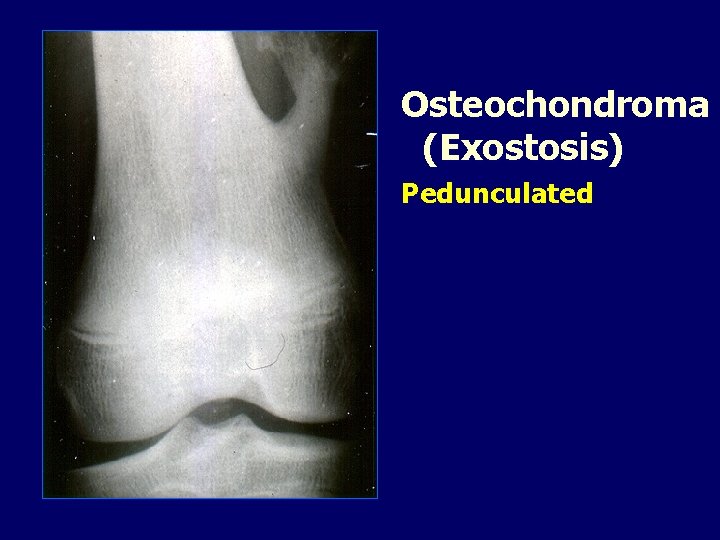

Osteochondroma (Exostosis) Pedunculated

OSTEOCHONDROMA • May be solitary or multiple. • Multiple…. . Diaphyseal aclasis. • ? ? Developmental abnormality of the metaphyseal area.